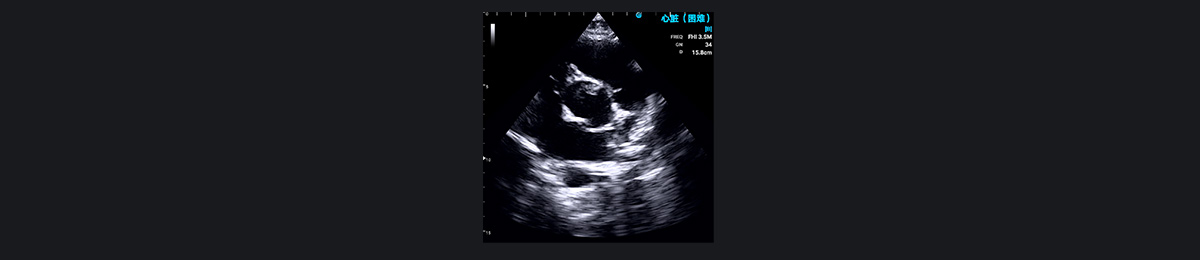

二叶式主动脉瓣